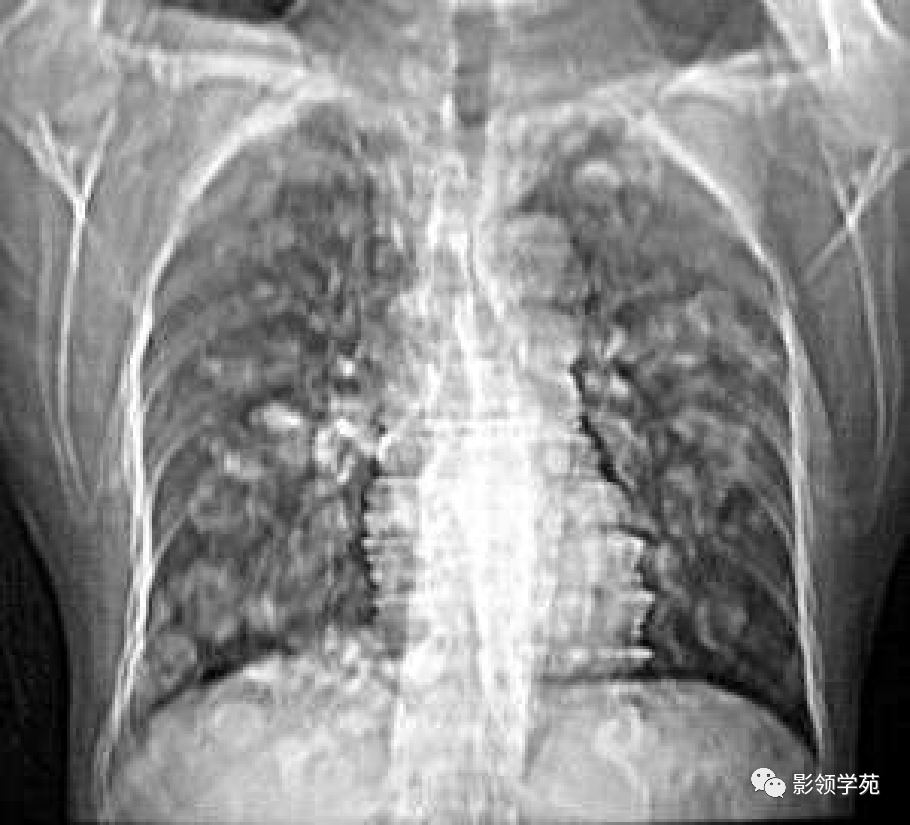

双肺淋巴道转移癌。胸部正位片示双侧中下肺野多发结节状及网格状高密度结节影,可见克氏B线(下图)

肿瘤外科患者,女55,9月前阴道不规则流血,诊刮术病检:子宫内膜浆液性腺癌(IV期),肺转移癌,盆腔淋巴结转移,骨转移,晚期无手术可能,省肿瘤TC方案化疗4周期,我院PAC方案化疗3疗程。

患者阴道不规则流血半年,于是做宫颈检查发现宫颈糜烂,涂片发现癌细胞,而考虑肺转移瘤!